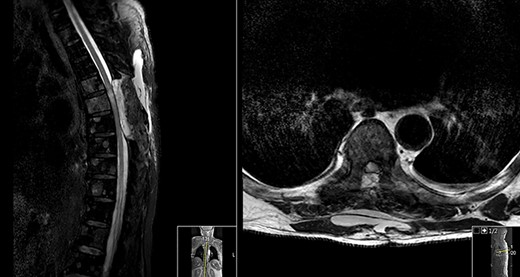

Spinal magnetic resonance imaging (MRI) (Fig. 1) showed an hyperintense contrast-enhancing abnormal mass at the level of T6 which occupied the left side of the spinal canal and compressed the spinal cord.